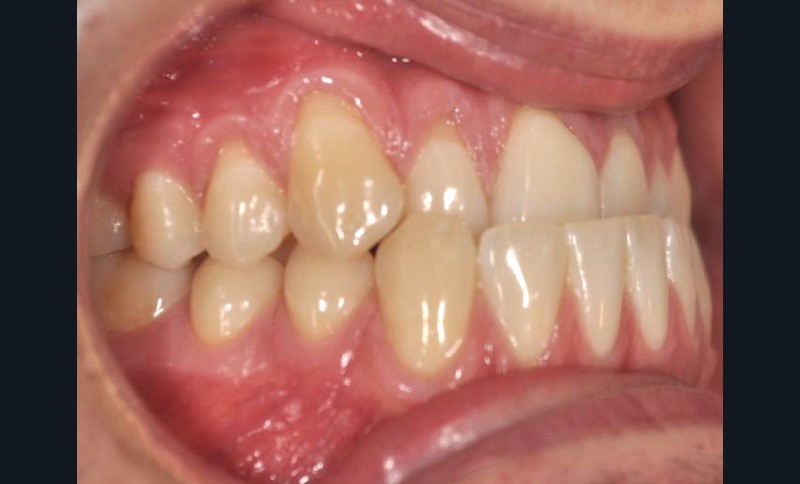

En intra-arcades (fig. 4-6), on note une classe III molaire et canine (fig. 4-5), trois plans d’occlusion, une déviation des milieux d’origine mandibulaire et un inversé articulé du bloc incisif maxillaire ; le biotype parodontal est fin, et l’on note des récessions gingivales (12, 13, 23, 33, 43) certainement dues à la mauvaise position et aux forces mal réparties lors de la mastication (fig. 5). L’arcade maxillaire est carrée avec une DDM antérieure (fig. 7), l’arcade mandibulaire étroite et allongée (fig. 8).